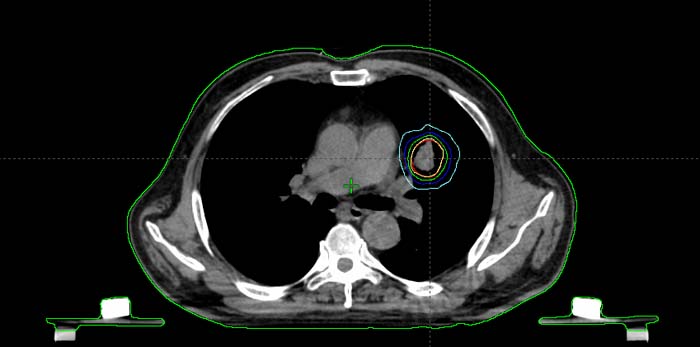

肺癌大分割放疗计划剂量线

- 肺癌大分割放疗计划剂量线